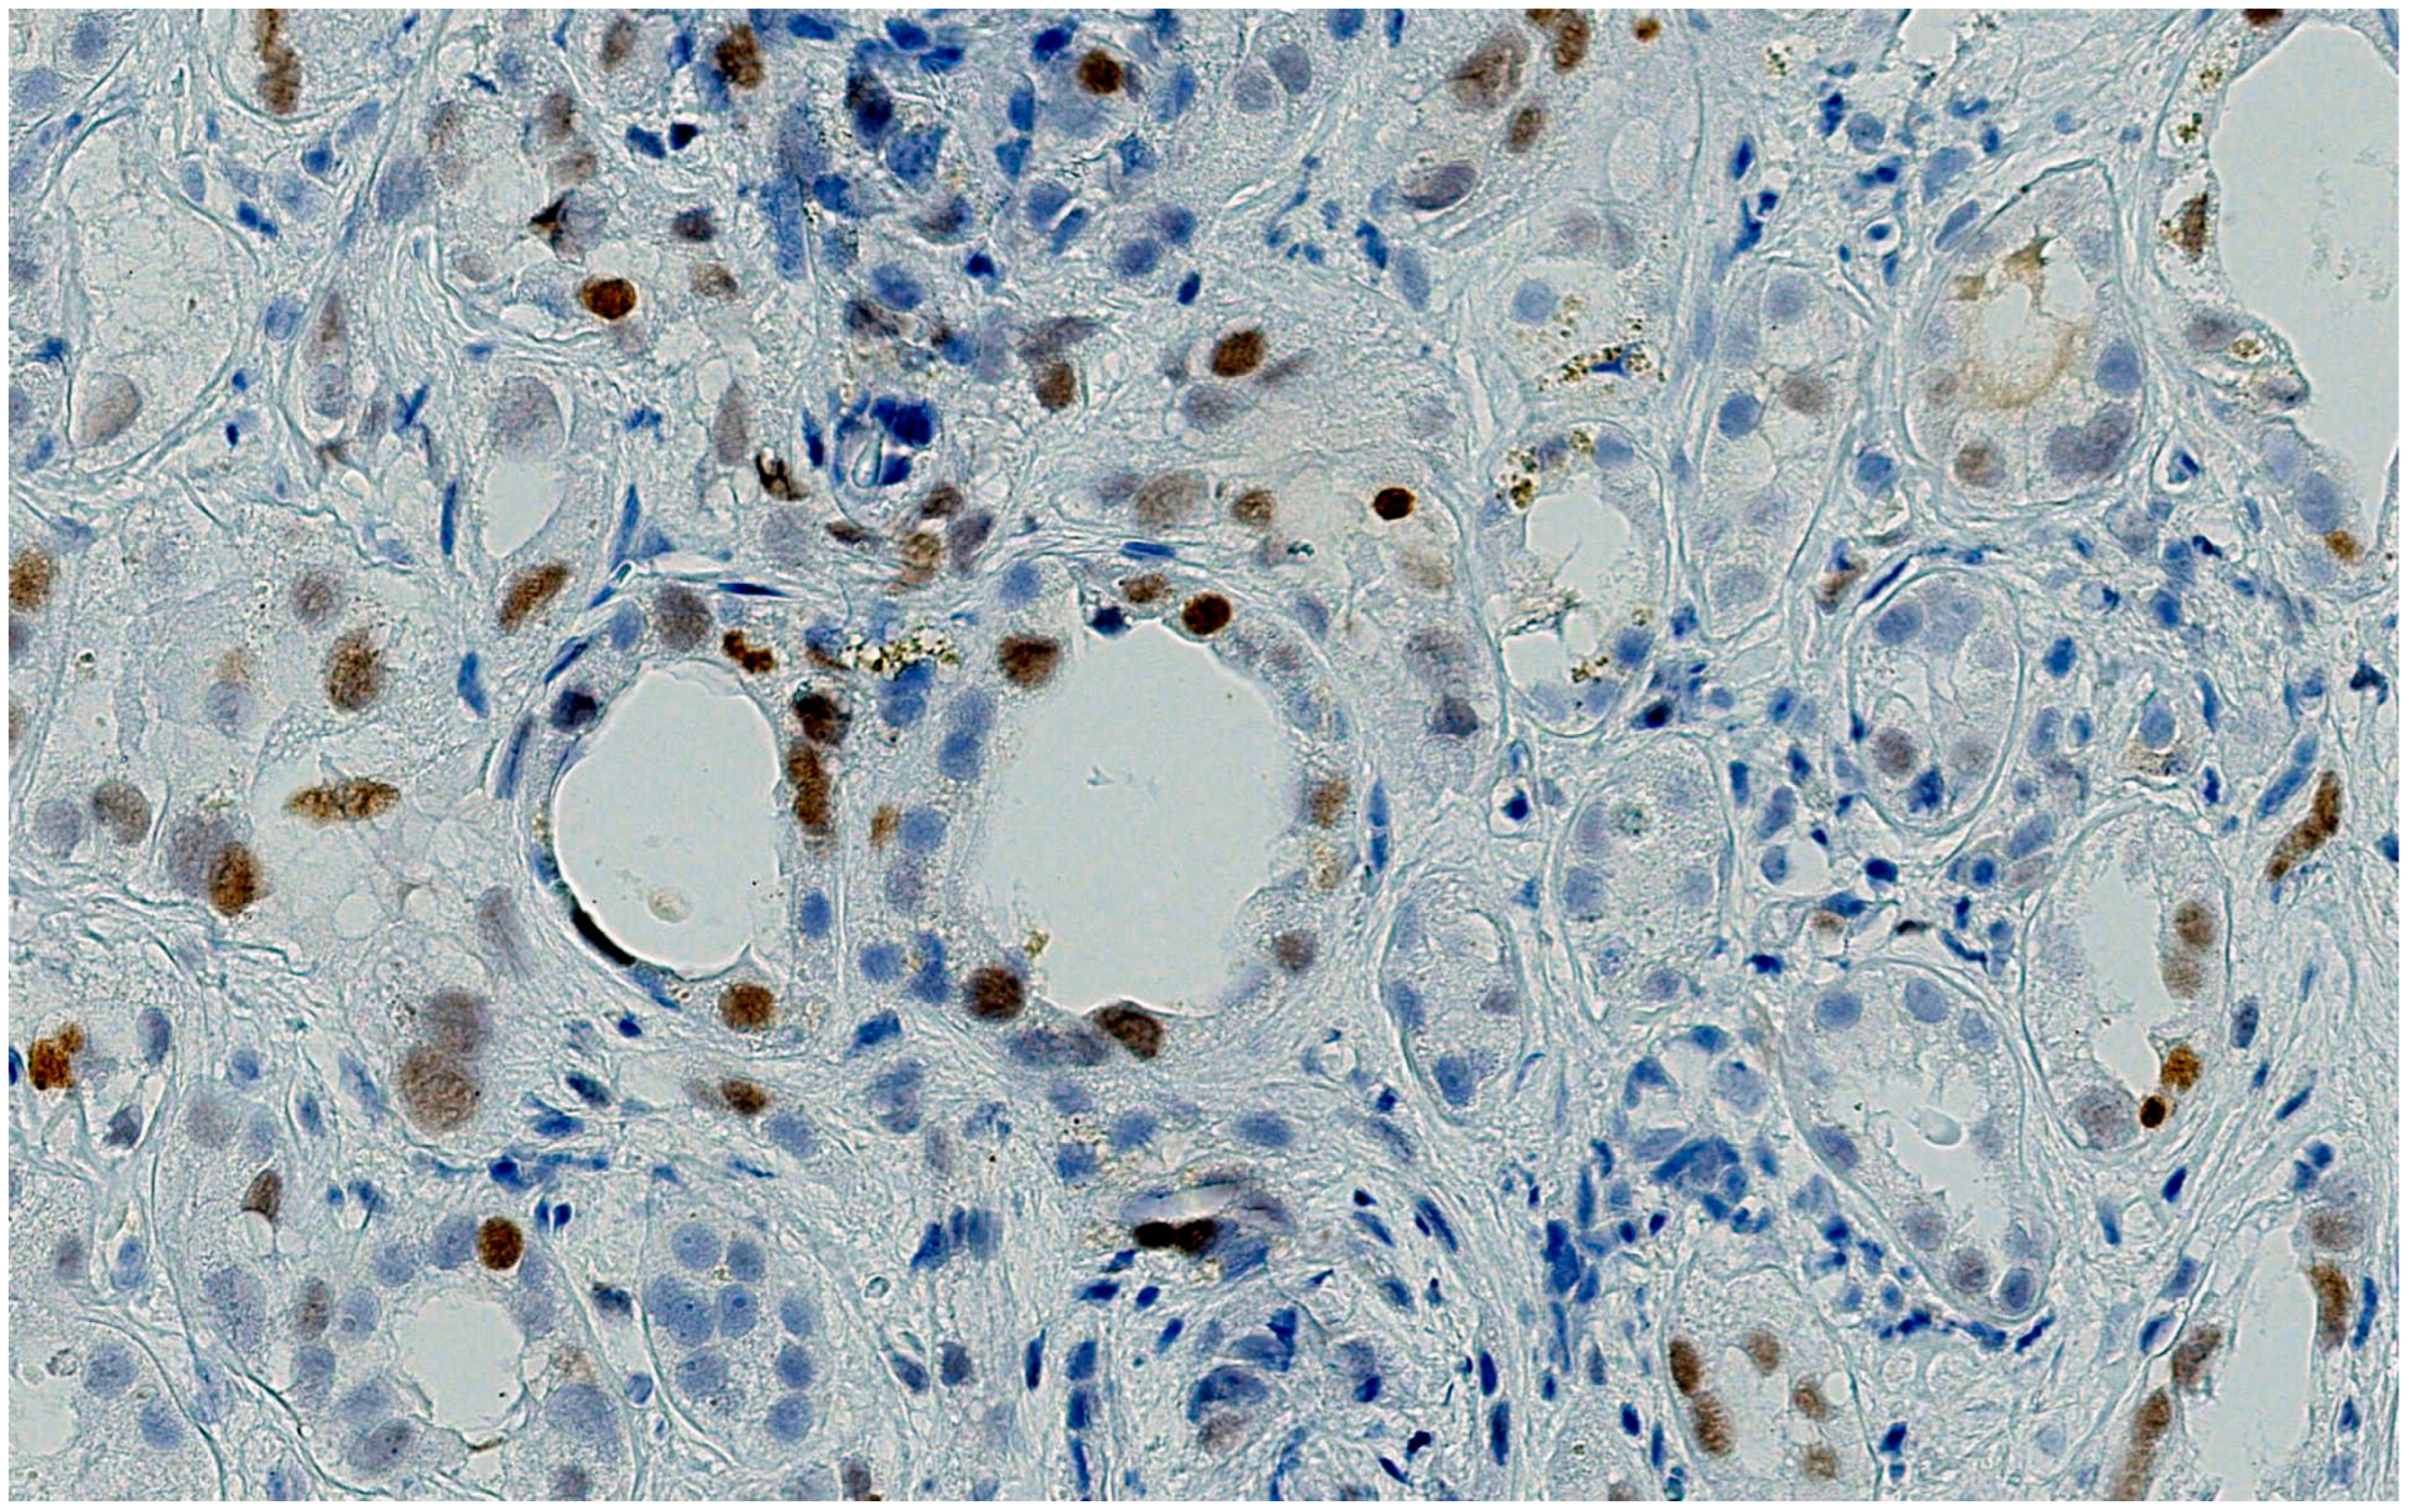

A thorough morphological examination including electron microscopy can assist a nephropathologist in distinguishing between ATN and AIN lesions with greater precision. However, both drugs can cause both pathological patterns, making it necessary to use advanced immunohistochemical techniques to determine which drug is responsible for the nephrotoxicity. In our case, the tubular expression of anti-PD1 was negative, while the tubular expression of p53 was positive.

Histological tubular expression with anti-PD1 is an experimental technique in nephrology. Cassol et al. [24] published a case series that tested its use on PD1-induced AIN. In the study conducted by Cassol, only monotherapies using checkpoint inhibitor drugs were administered to patients. Among those who received anti-PD-1 therapy and were diagnosed with AIN based on renal biopsy samples, PD-L1 staining was found to be positive not only in inflammatory cells but also in tubular epithelial cells. If PD-L1 staining is negative or is observed only in inflammatory cells within fibrotic areas, then it is likely that the AIN is associated with causes other than anti-PD-1 therapy.

Our group also utilized this technique to customize the diagnosis and treatment of anti-PD1-induced AIN, and the results were in line with those of Cassol [25]. By identifying PDL1-negative tubular damage in our patient, we were able to demonstrate that the damage was caused by platinum and not pembrolizumab-mediated.

Figure 4. An example of the pattern of PDL-1 expression in checkpoint inhibitor tubule-interstitial nephritis: A brisk expression, in both inflammatory and tubular epithelium, in correspondence of the inflammatory foci is evident.